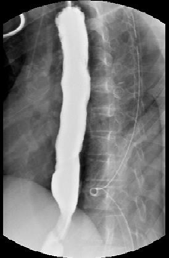

attempted and unsuccessful. Computed tomography angiography

(CTA) was obtained that showed hypoattenuation of the gastric

conduit along the aorta near the area that was cauterized [Figure 1].

Figure 1: CTA demonstrating hypoattenuation of the gastric conduit along the

aorta near the area that was cauterized with concern for aortoenteric fistula.